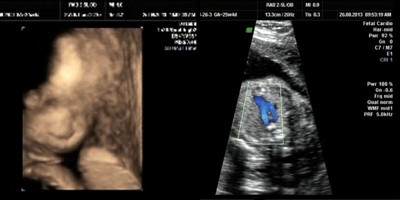

2、jing确筛查先天性畸形,多方位、多角度地观察胎儿生长发育情况,为早期诊断胎儿先天性心脏疾病和先天性体表畸形提供准确的科学依据,让众多的准妈妈安心。

3、立体、直观地拍摄的高清晰度宫内“写真”和动态录像,将宝宝的一举一动刻录成DVD,保留更完整的生命印迹。

四维彩色超声诊断仪能自动为胎儿进行宫内拍“写真”和动态录像,为众多的准妈妈增添了安心和情趣。不再是仅仅感觉宝宝的呼吸和运动,而且可以亲眼目睹他们的一举一动和乖巧的秀容。

杭州玛莉亚妇产医院的专家说,四维彩超蕞大的功用还是在于筛查胎儿畸形,可以jing确筛查腹中胎儿所患的如唇腭裂等非常细小的畸形。过去的B超设备只能检查胎儿的生理指标,而四维彩超还能对胎儿的体表进行检查, 如唇裂,脊柱裂,大脑、肾、心脏、骨骼发育不良等,以便尽早的进行治疗。

更为重要的是,四维彩超能够多方位、多角度地观察宫内胎儿的生长发育情况,为早期诊断胎儿先天性体表畸形和先天性心脏疾病提供准确的科学依据。四维彩超检查时间在准妈妈在24-30周期间做四维彩超检查蕞佳。

传统的三维彩超是静态地观测胎儿,不能刻盘,而四维彩超是动态的,能自动为胎儿拍摄动态录像,不仅能让您感受到宝宝的呼吸和运动,还能亲眼目睹到胎儿乖巧的面容和一举一动的表现。